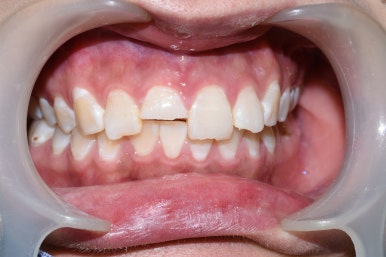

Case2.

위의 케이스 1과 동일한 분 아니냐고요?

아닙니다... 이렇게 저희 치과에 앞니가 깨진 분이 많이 오신다구요... (동의한 사진만 공개해요)